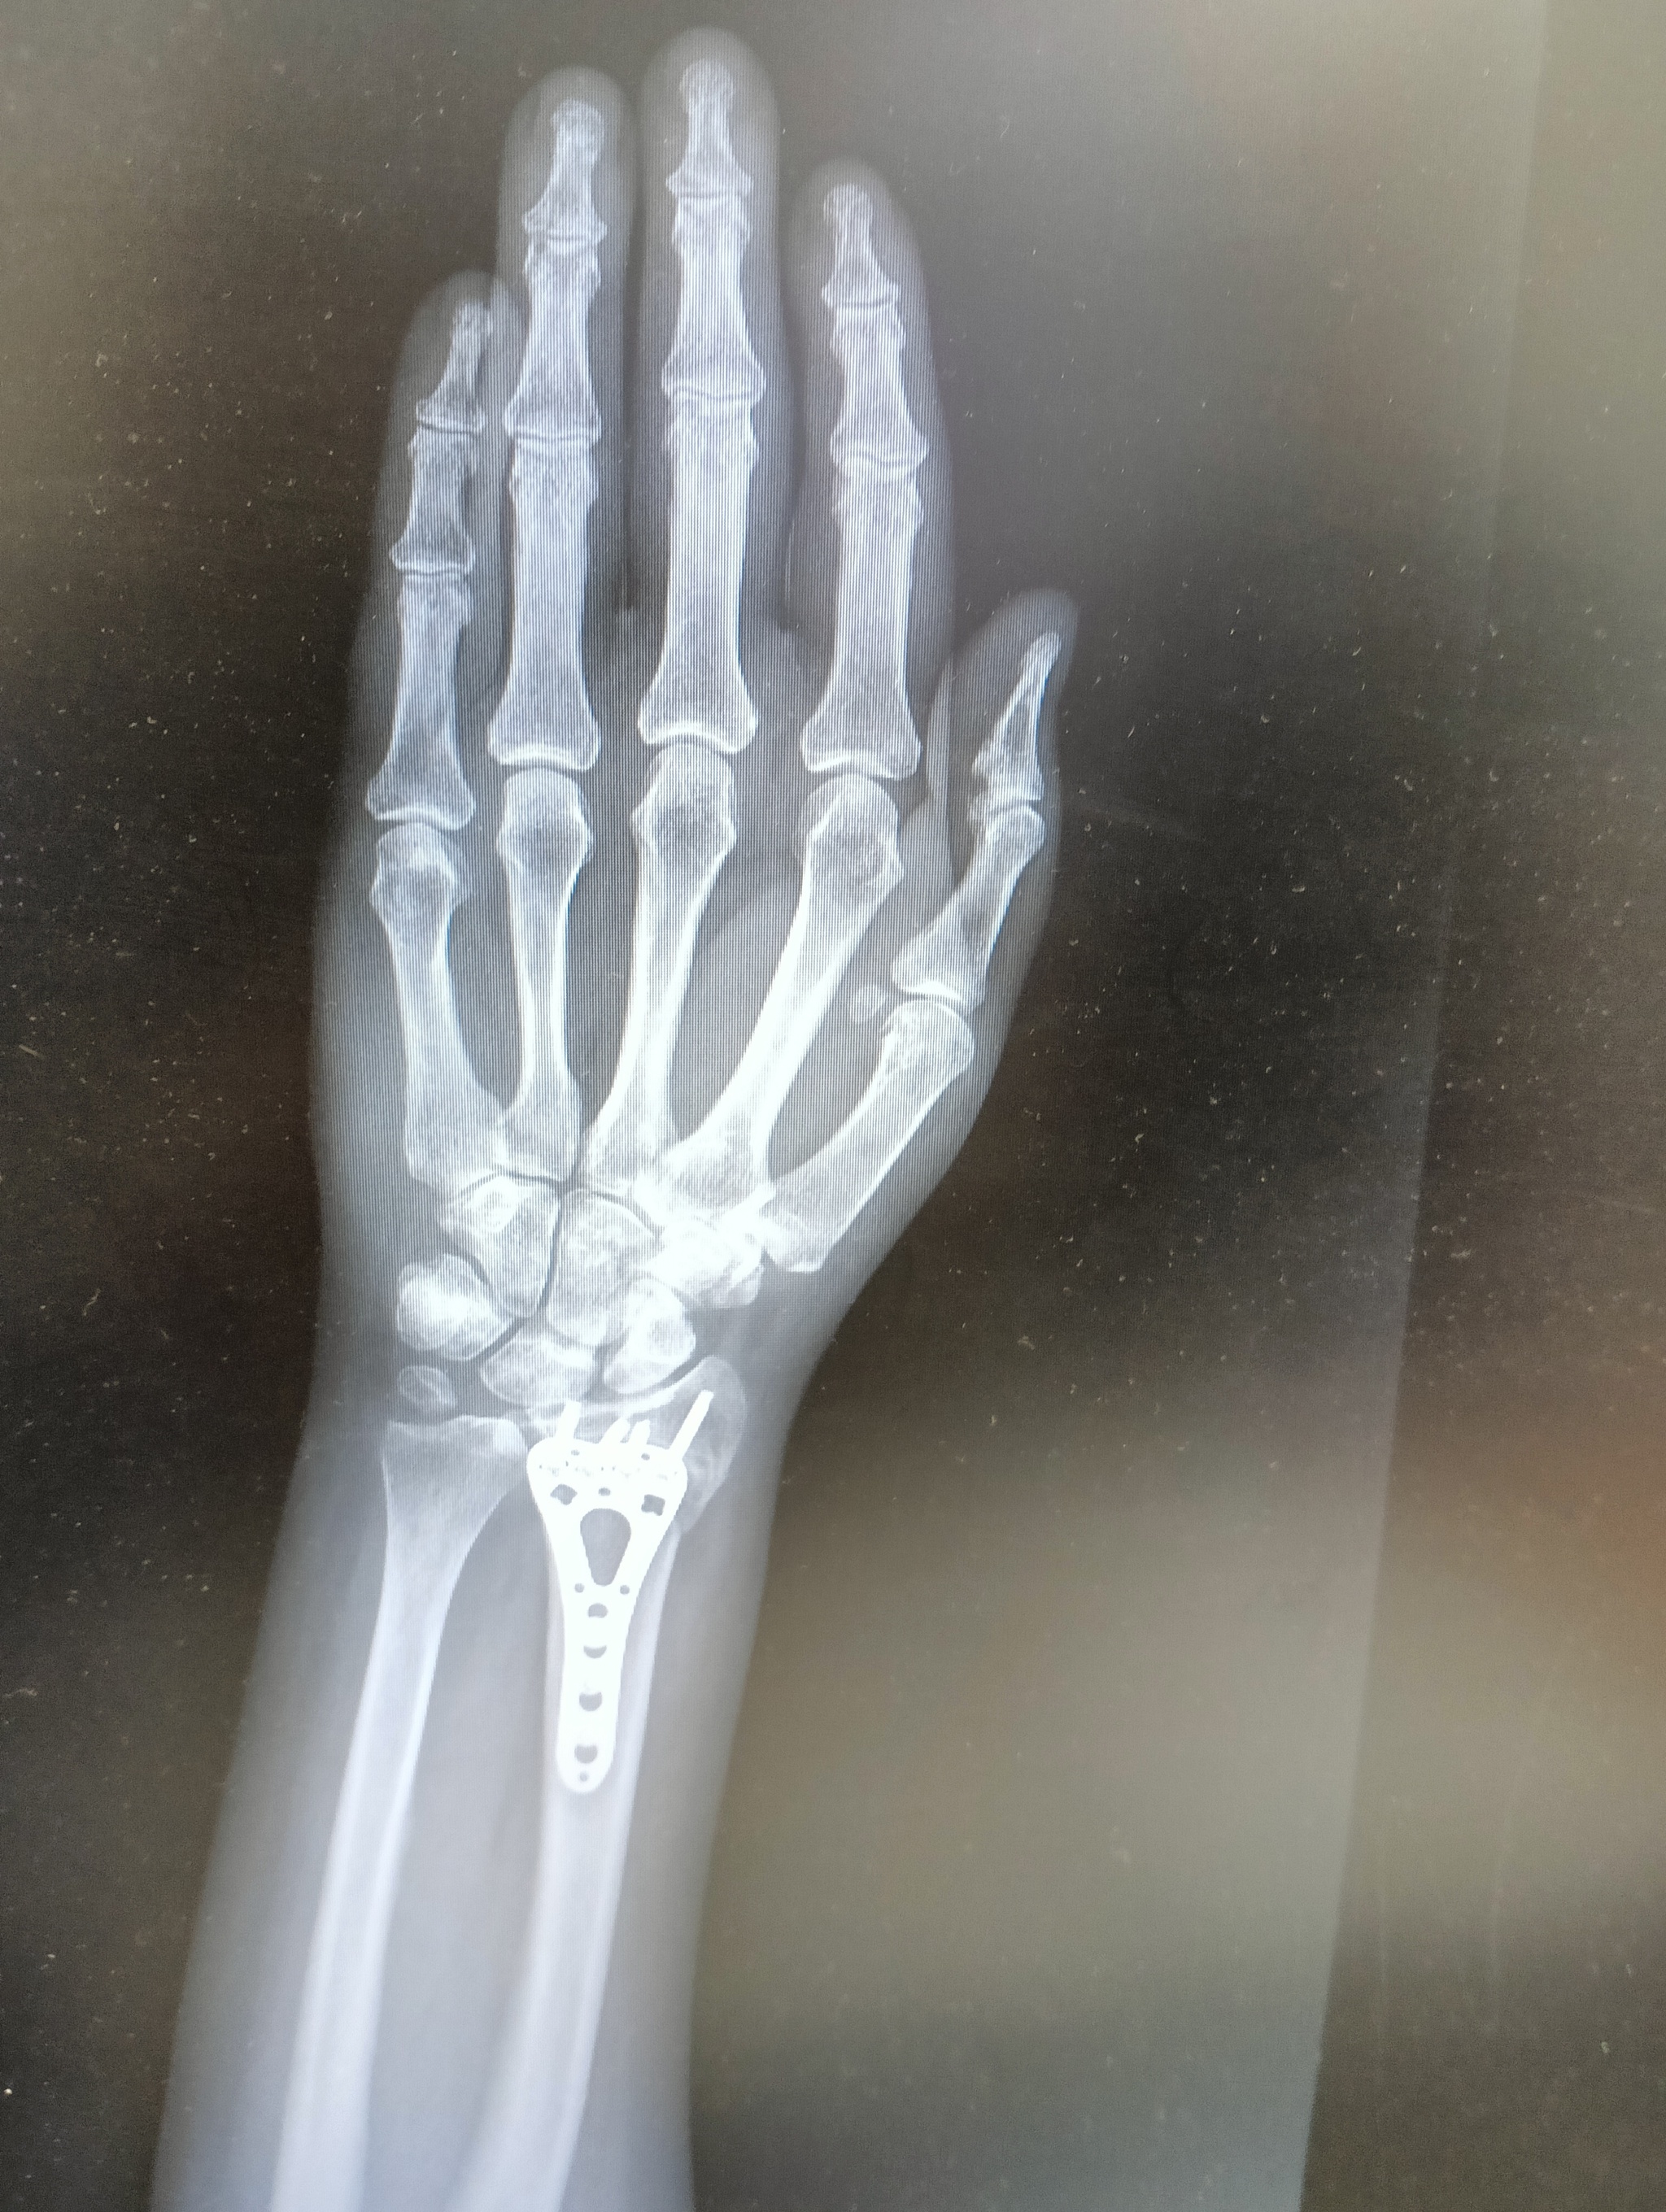

22 июля я неудачно упала и получила оскольчатый перелом дистального метафиза лучевой кости со смещением отломков более чем на 1/2 ширины диафиза. Открытый перелом шиловидного отростка локтевой кости. Была месяц в гипсе, но ничего не срослось. Диастаз костных отломков стал до 4 мм. Локтевая ушла в сторону на 5 мм. На 3 месяц после перелома мне сделали операцию, поставив титановую пластину. Сегодня сделала ренген и получила вот такой результат: Застарелый сомнительно консолидирующийся перелом дистального метафиза правой лучевой кости в условиях накостного МОС. Помимо отрыва шилообразного отростка локтевой кости, видно, имеется разрыв дистального радио-ульнарного сочленения.

верхние ффото через 2 месяца после перелома, потом после операции и 2 нижние - сегодня